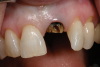

Fig 5. Successful final clinical result of the implant restoration and adjacent teeth.

Figure 5